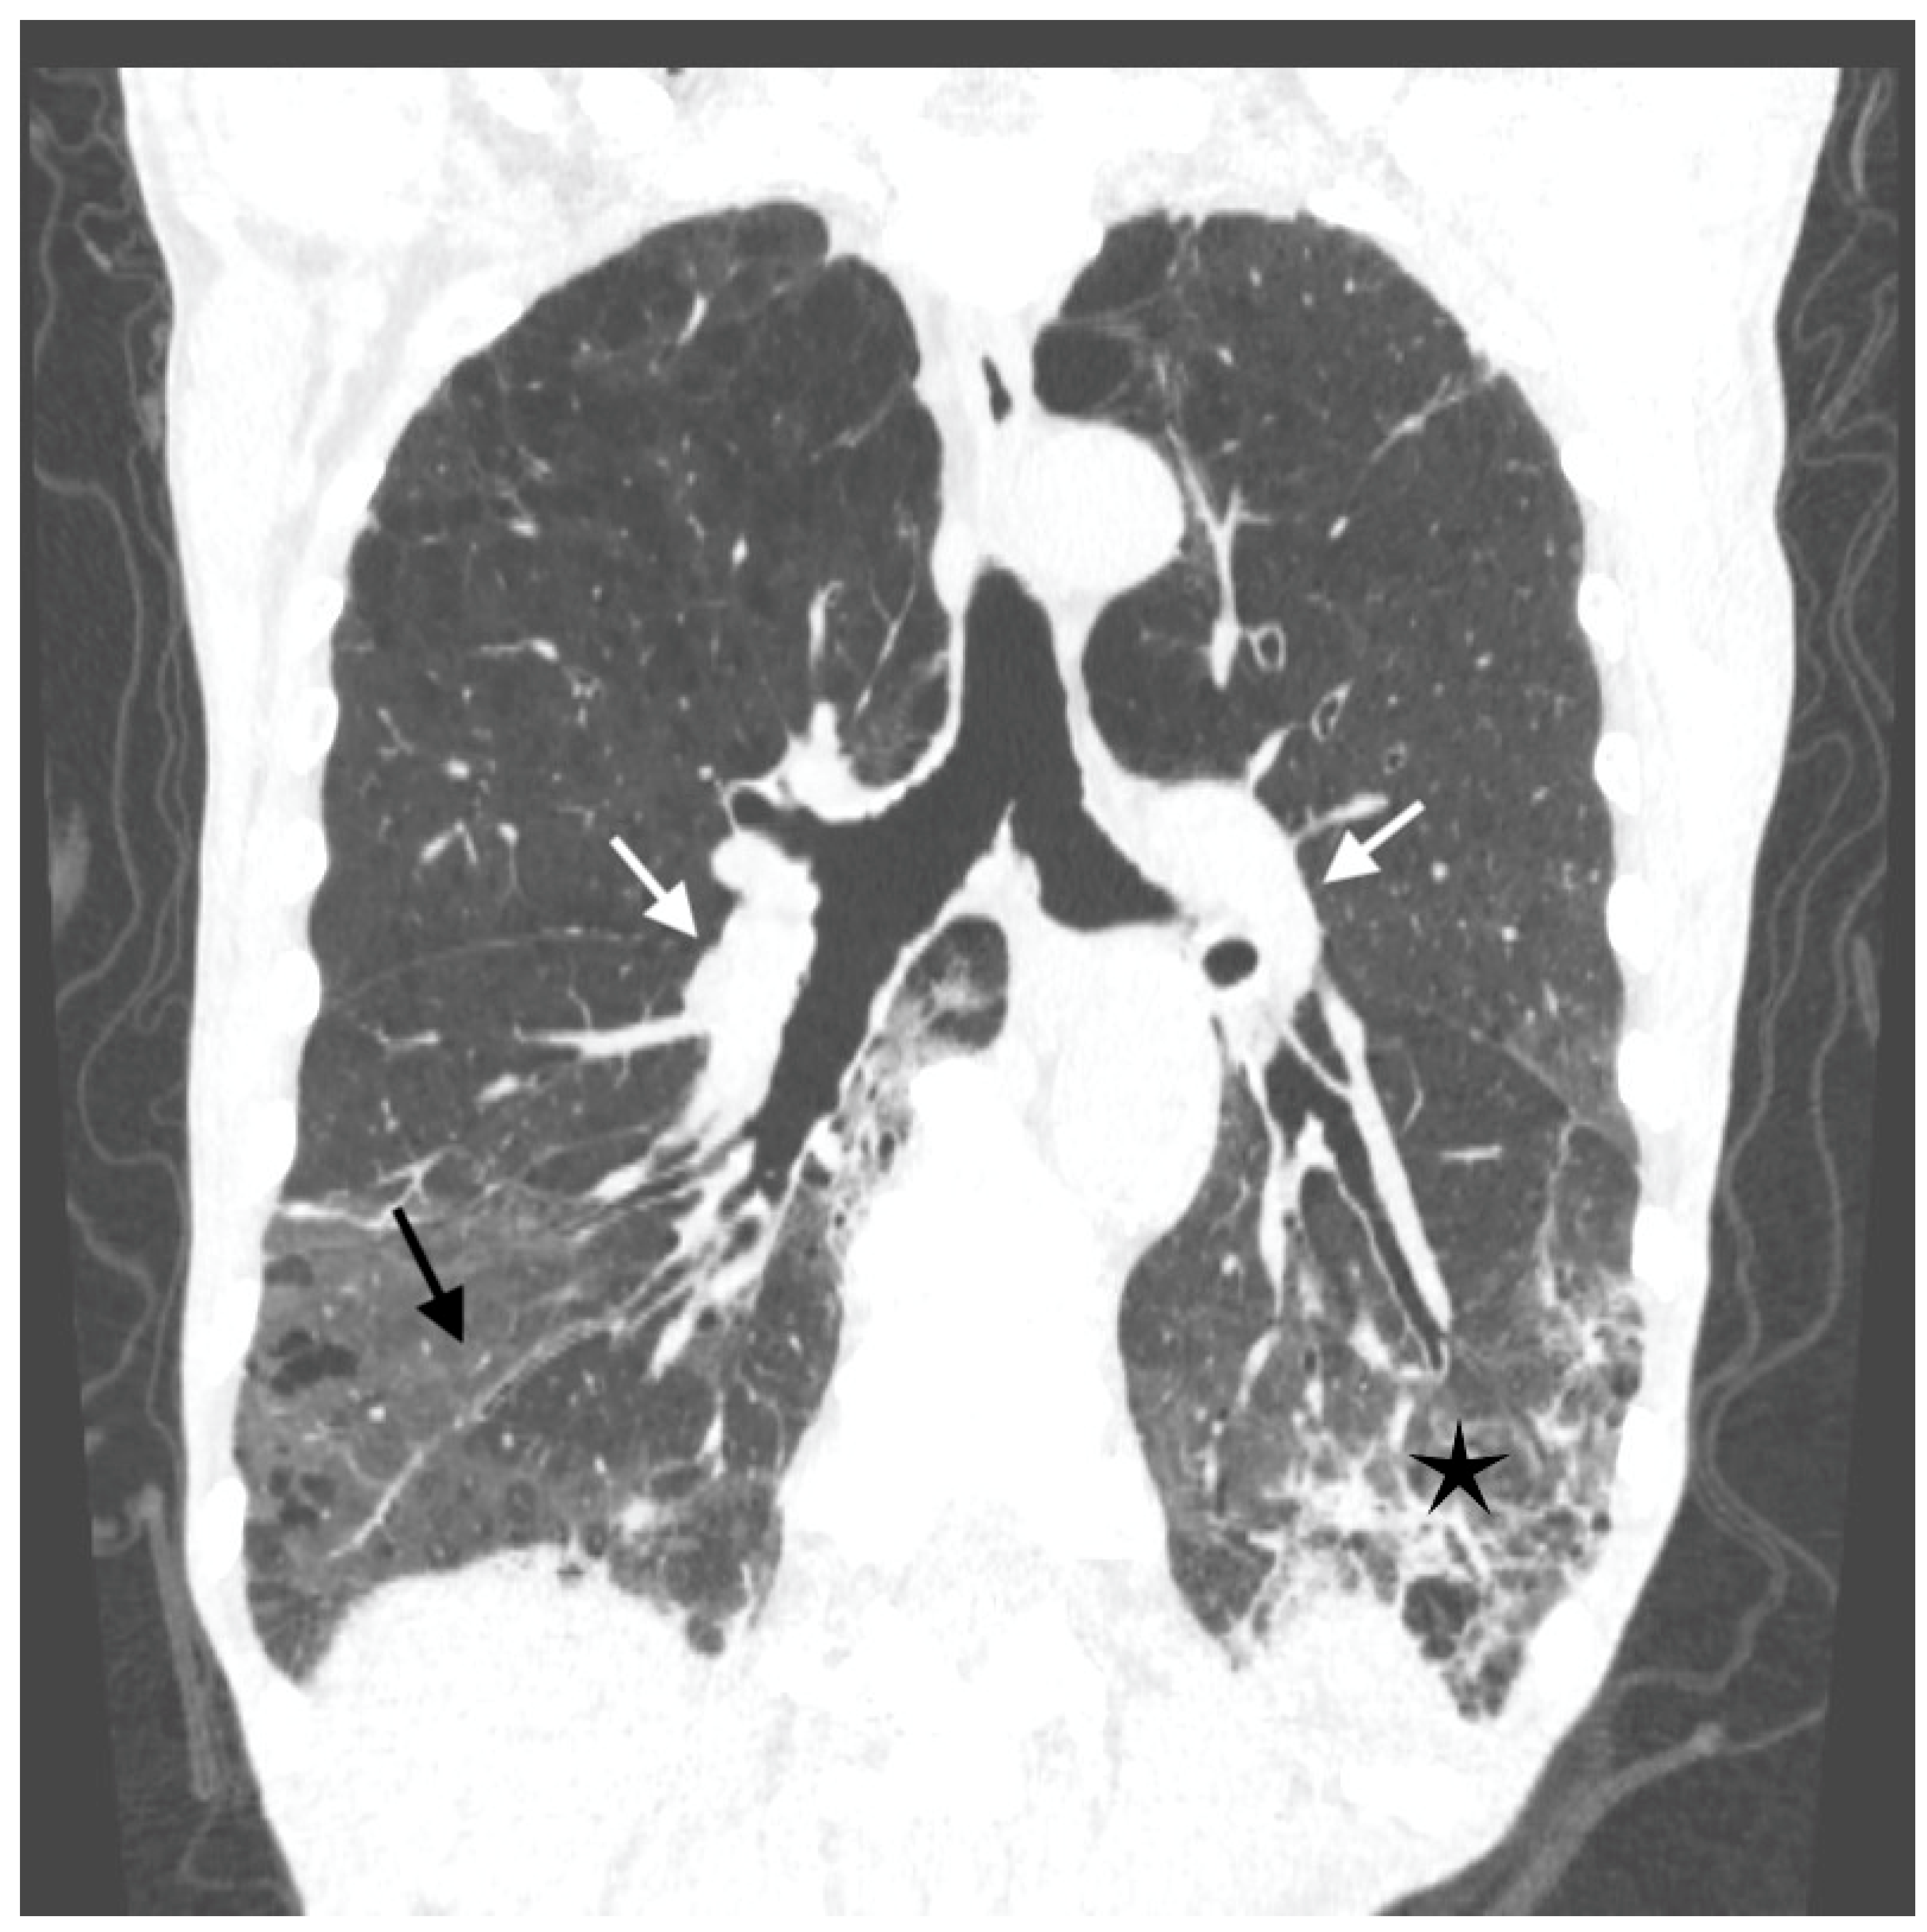

Antibiotic treatment was modified—ceftriaxone was withdrawn and meropenem with levofloxacin were started. A few days later, dyspnea increased suddenly. The cardiac arrhythmia was noted on physical examination, and the electrocardiogram (ECG) revealed atrial fibrillation. The sinus rhythm recovered spontaneously after a few hours. Despite that, the respiratory failure progressed, and oxygen delivery was gradually increased to maintain SpO2 above 90% (maximal oxygen flow was 15 L/min. through the face mask with an oxygen reservoir). A CTPA was repeated and excluded pulmonary emboli. Aortic atherosclerosis without aneurysm and bilateral hilar adenopathy was found. Massive bilateral ground glass opacities in the middle and lower parts of the lungs accompanied by parenchymal infiltrations and bronchial walls thickening were demonstrated (Figure 2)—the lesions progressed compared to the previous CTPA. This presentation suggested alveolar hemorrhage or infection.

Figure 2. Computed tomography (CT) scan of the chest showing bilateral hilar adenopathy (white arrows), massive bilateral ground glass opacities in the middle and lower parts of the lungs (black arrows) accompanied by parenchymal infiltrations (black asterisks) and bronchial walls thickening.

The radiologic recognition of BCG-related lung disease is also difficult. Lung involvement may present either as a result of the hematogenic spread of M. bovis, mimicking “miliary tuberculosis” [7,18,19,20,21,22] or—more frequently—as interstitial pneumonitis with bilateral ground glass opacities [6,13,23]. In children, BCG infection occurs rarely after vaccination and may present as pneumonic infiltrates and lymphadenopathy [24]. Ground glass opacities are usually assessed as hypersensitivity reactions rather than infection [25,26]. In our patient, radiologic changes in the lungs were mostly interstitial, micronodules were few, ground glass opacities and infiltrates dominated in CT scan, hilar lymph nodes enlargement was also present—the whole presentation at the first lung CT scan was interpreted as NSIP. Even at later stages, after lesion progression, the ground glass opacities predomination caused doubts among radiologists, if the BCG-osis is the most probable differential diagnosis. The time of symptom onset in the middle of the severe COVID-19 pandemic and quickly progressive respiratory failure, suggested the possibility of SARS-CoV-2 lung disease, as well. Nevertheless, repeated PCR tests for SARS-CoV-2 were negative.